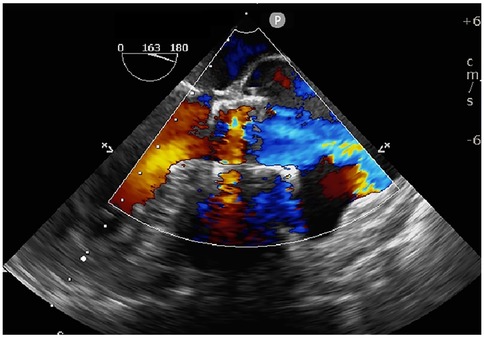

Transapical access was achieved via a small intercostal incision over the left ventricular apex, using a dedicated delivery catheter and J-valve system. Under fluoroscopic guidance and TEE monitoring, three U-shaped nitinol graspers were deployed into the aortic sinuses, demonstrating stable morphology and positioning. A 29 mm self-expanding valve was then deployed and securely seated within the graspers. Intraoperative TEE confirmed optimal prosthetic position and stability, with no paravalvular regurgitation; notably, two ACTs ruptured, neither compromising valve stability (Figure 2; Supplementary Video S4). The TAVR valve was subsequently decoupled from the delivery system. Following delivery system retrieval, aortic root angiography and TEE confirmed absence of AR, paravalvular leakage, or coronary obstruction, with stable stent position and normal prosthetic function (Figure 3; Supplementary Video S5).

Figure 2. Three-dimensional TEE post-TAVR showing the self-expanding prosthetic valve with ruptured aortic chordae tendineae (white arrows) at the aortic root.